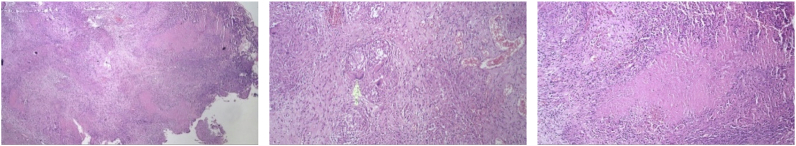

Fig. 6.

Histopathological findings on third case.

Bacteriological signs and histopathological findings are gold standard to establish ITB. Sharma et al. studied 70 cases of abdominal TB and found evidence of active or cured lesions in chest X-ray in 22 cases (46%). Biopsy methods include endoscopy, gastrointestinal mucosal biopsy, percutaneous biopsy, guided endoscopic ultrasound biopsy, and surgery (open or laparoscopic). In all three of these patients a biopsy was performed and histopathological examination confirmed a chronic granulomatous inflammation with caseous necrosis caused by TB. In ITB, granulomas are presented as larger amount and larger size (>200 μm) in the mucosa and submucosa. Positive PCR and ascites fluid tests were found in 72% and 87.5% of ITB patients [[12], [13], [14]]. Among bacteriological examination, PCR analyses of biopsy specimens have been shown to be a valuable tool in improving diagnostic yield, with a high specificity, 95%. It has also been found to be more sensitive than AFB stain and Mycobacterium tuberculosis culture [4]. However, drawback of PCR utilization is the uncommon availability, notably on developing countries such as Indonesia.